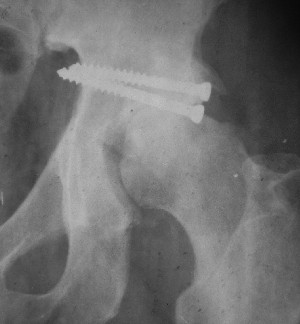

Послеоперационный снимок прямой 5/05/03

Послеоперационный снимок боковой 5/06/03

Больной 18 мая 2003 года в автоаварии получил перелом левой вертлужной впадины, вывих бедра. Госпитализирован в один из стационаров области.Вывих вправлен. В последствии бедро вывихивалось еще дважды. На консультацию был представлен снимок от 19.05.03г., больной переведен к нам 3.06.03г. Снимок при поступлении - перелом впадины, задне-верхний вывих бедра. 05.06.2003 г. выполнено открытое вправление вывиха левого бедра и остеосинтез стенки вертлужной впадины двумя винтами. Послеоперационный период без осложнений. Объем движений в левом тазобедренном суставе восстановился полностью. Выписан на амбулаторное лечение в удовлетворительном состоянии с рекомендациями 3 месяца ходить на костылях без нагрузки на оперированную конечность. На контрольных рентгенограммах левого тазобедренного сустава 13.10.2003 г. - признаки консолидации перелома; плотность, форма головки и состояние суставных поверхностей удовлетворительные. Разрешена дозированная осевая нагрузка, на конечность с использованием дополнительной опоры. 19.12.2003 г. больной обратился с жалобами на боли в левом тазобедренном суставе. На рентгенограммах левого тазобедренного сустава 19.12.2003 г., 20.02.04г. - асептичекий некроз головки бедра. 5.04.04г. - эндопротез. Сейчас ходит без трости, не хромает. Особенность эндопротезирования - при удалении винтов прослежена линия перелома заднего края впадины и предложено установить чашку несколько меньшего диаметра, чтобы она была покрыта несломанной частью.